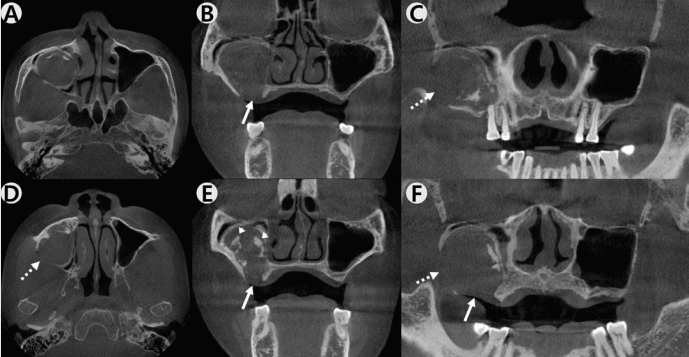

이 증례보고는 조선대학교치과병원 기관생명윤리위원회에서 승인 번호 CUDHIRB 2401 003으로 승인을 받았다. 72세의 여자 환자가 1년 전 우측 상악 제1,2 대구치 발거 후, 수개월 동안 지속해서 해당 부위에서 염증 삼출물이 나온다는 증상을 호소로 조선대학교 치과병원에 내원하였다. 처음 내원했을 때, 양측 상악 제1, 2대구치(#16,17,26,27)는 결손된 상태였고 임상 검사에서 발치 후 치유가 완전하게 진행된 정상 구강 점막의 형태를 관찰할 수 있었다. 환자는 전신 질환으로 고혈압과 당뇨가 있었으며, 안면부 외상이나 상악동 수술 등의 병력은 존재하지 않았다.파노라마방사선영상에서 우측 상악동 내부 대부분의 공간이 방사선불투과상으로 채워져 있는 것을 관찰할 수 있었다(Fig. 1). 또한 반대측과 비교하였을 때 우측 상악동 저의 경계가 분명하지 않고 치조골의 골밀도가 감소된 소견을 보였다. 추가적인 평가를 위해 cone-beam computed tomography(CBCT)에서 얻어진 영상을 axial, coronal, panoramic plane으로 재구성하였다. 재구성된 영상에서 우측 상악동 내부를 채우고 있는 장경 3.5 cm정도의 낭종 병소가 관찰되었으며, 상악동의 전방 및 후외측 골이 팽융되고 상악동의 후외측 경계와 상악 치조골이 병소에 의해 소실된 소견이었다(Fig. 2). 병소의 경계는 대체적으로 잘 구분되고 타원 형태의 구조를 보였다. 경계 부위에서는 비후된 형태의 경화성 골 변연이 관찰되었고 병소 내부에서는 불규칙하고 무정형의 석회화가 산재되어 있었다. 술후상악낭(postoperative maxillary cyst)과 석회화치성낭(calcifying odontogenic cyst)을 감별진단으로 고려하였다.본원 구강악안면외과에서 전신마취 하 구강 내 치조정측 접근을 통한 수술적 적출을 시행하였는데, 수술하면서 우측 상악동에서 농이 배출되는 양상과 육안상으로 볼 때 육아종처럼 보여지는 종괴(granulative mass)를 관찰할 수 있었다(Fig. 3). 수술 후 병리조직학적 검사 결과, 광범위한 골화를 동반한 콜레스테롤 육아종(cholesterol granuloma with massive ossification)으로 진단되었다(Fig. 4).환자는 수술 후 약 2주 정도 수술 부위에 대한 관리와 상악동의 배농 및 환기 상태의 유지를 위해 추가적인 처치를 받은 후 퇴원하였고, 수술 8개월 후 시행한 CBCT 검사에서 재발과 관련된 소견이 관찰되지 않았으며(Fig. 5) 현재까지 별다른 합병증 없이 추적 관찰 중이다.

Figure 2.

Expansile, soft tissue density mass is located in the right maxillary sinus from the reconstructed CBCT axial (A,D), coronal (B,E), panoramic (C,F) planes. There is an amorphous calcification within the mass (arrow head). Loss of the floor of the maxillary sinus (arrow) is observed and posterolateral wall of the maxillary sinus is also absent (dashed arrow).